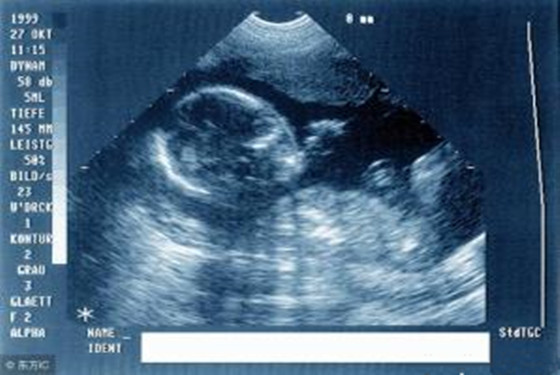

我们先来了解一下关于双顶径的定义,双顶径(BPD)说简单点就是胎儿的胎头尺寸,也就是指头部左右两侧之间最宽部位的长度,医生常常用这个来衡量孩子的发育情况,来判断是否能够顺产还是剖腹产。

胎儿的双顶径尺寸会随着他的成长而变化,通常怀孕7个月时BPD约为7.0厘米;怀孕8个月时BPD为8.0厘米;孩子足月时BPD应达到9.3厘米或以上。